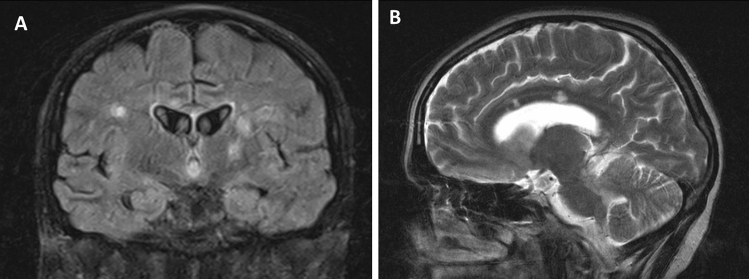

Callosal and/or peri-callosal lesions on brain MRI were seen in all patients (Fig. 1). Only 1/14 patient had CSF leukocytosis (26 lymphocytes) and 12/14 patients had raised CSF protein. Oligo-clonal bands were absent in all 13 patients who were tested for it.

Fig. 1.

MRI changes in Susac syndrome MRI sequences of showing callosal (arrows), periventricular and thalamic lesions in coronal FLAIR (A) and sagittal T2W (B) images

Rennebohm et al. have suggested that the microinfarcts or “snowball” (larger lesions) appearance of the mid-corpus callosum and/or the “string of pearls” (micro-infarcts of the internal capsule) is perhaps sufficient to diagnose Susac Syndrome without evidence of hearing impairment or BRAOs [9, 31]. Although callosal lesions are included in the diagnostic criteria [3], they are not always present [32]; they are typically seen in the central fibres and splenium without involving the undersurface unlike MS [33]. The callosal roof is often involved giving an ‘icicle’ look to the lesions [7]. Callosal lesions are usually small and as a consequence of occlusion of the small (less than 100 µm) precapillary arterioles [33]. The periventricular white matter as well as the deep grey matter is also affected [7]; the deep grey matter can be involved in up to 70% of cases [5].

Leptomeningeal involvement can be seen in up to 33% [5] (Fig. 1). The correlation to headache however could not be established in our series. A plausible explanation is the variable course of the condition. Moreover, the lack of sensitivity of post-contrast T1-weighted images as compared to post-contrast fluid-attenuated inversion recovery (FLAIR) sequences may provide a reasonable explanation [34]. Spinal involvement has rarely been reported in Susac Syndrome [35, 36]. Small vessel or perivascular enhancement on high-resolution intracranial vessel wall MRI has been reported in Susac syndrome [37]. Degradation of fibres in the genu of corpus callosum, using Diffusion Tensor Imaging (DTI), is thought to be specific for Susac syndrome [38] and can potentially be a future diagnostic tool.